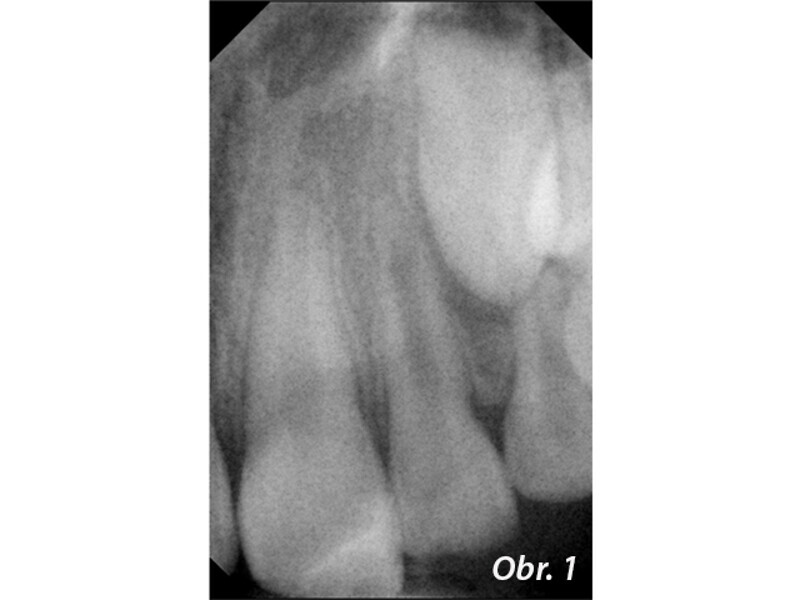

Endodontické ošetření zubů s nedokončeným vývojem kořene